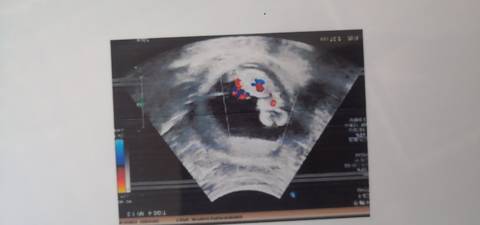

第一胎是儿子,第二胎想要女宝,但一切天注定,什么都喜欢,好奇男宝女宝大家帮忙猜猜看

journal_insert_pic_1690454134journal_insert_pic_1690454140

通过这些是看不出来的,而且也不准确,在怀孕期间,我觉得只要宝宝发育好的话,还是不要想太多了,男孩女孩都一样的。

你好。我们是判断不了男宝宝跟女宝宝的,孕期定期检查,我觉得宝宝健康就好的。祝心想事成 。

#妈妈问答大赛#不是医生是看不出来的,不过怀男宝女宝感觉是有区别的,怀孕反应不一样